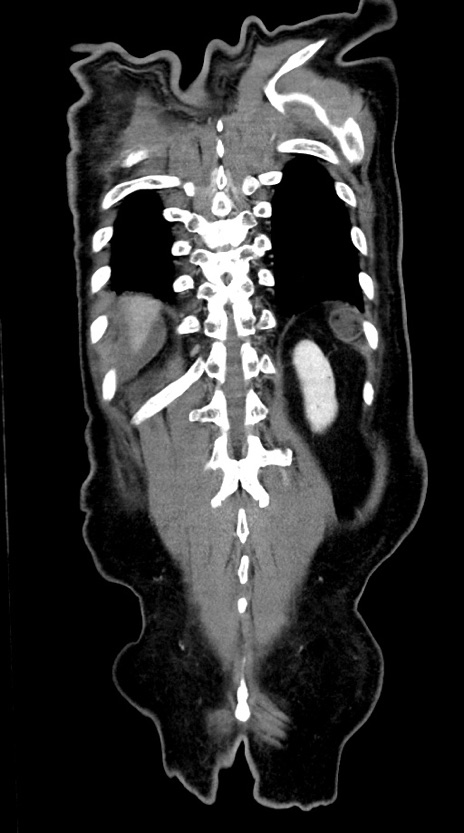

症例28(冠状断像)

【症例】60歳代男性

【現病歴】胃癌にて胃全摘後。食思不振が悪化し、夜中に嘔吐することがある。

【既往歴】胃癌、胃全摘、脾摘、胆摘後